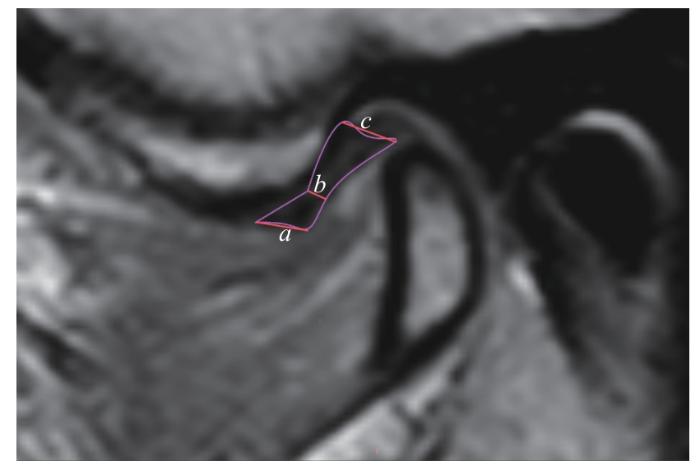

将扫描所得信息导入电脑,使用软件DICM Viewer 3.7.1进行阅片及测量。定位像在轴状层面上选择,斜矢状位的定位线应垂直于髁突的横轴(髁突内外极连线),整个髁突前后斜面及邻近翼外肌应包括在斜矢状位24图1)。

图1

图1   MRI阅片时的定位平面

Note: PDWI images. A. Axial plane. l1—the transverse axis of the condyle (the line connecting the internal and the external poles of the condyle); l2—the positioning plane perpendicular to the condylar transverse axis. B. Oblique sagittal plane. a—condyle; b—articular disc; c—lateral pterygoid muscle.

Fig 1   Positioning planes for MRI image reading